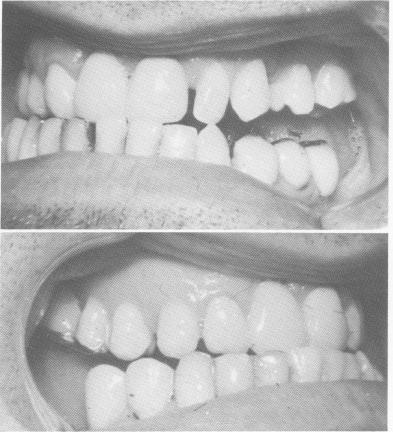

Fig. 15-24. Posterior gold veneer crown castings and Duralay anterior acrylic transfer copings are seated.

Fig. 15-25. The intermaxillary space was posteriorly divided equally by first lengthening the maxillary castings to one-half the distance.

3 Upper gold crown castings, Duralay acrylic transfer copings

4 Lengthening of maxillary castings to one-half the distance